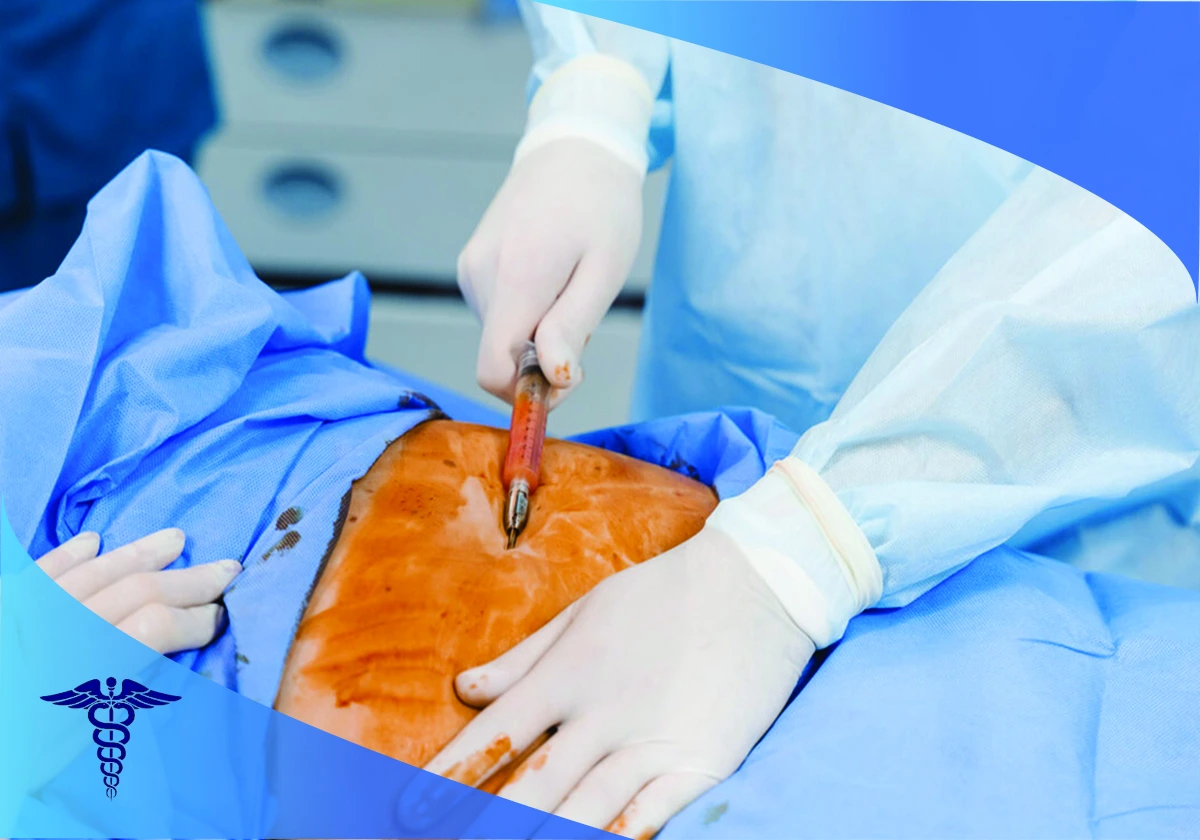

با توجه به اینکه عمل جراحی ابدومینوپلاستی در شیراز یک عمل تهاجمی محسوب میشود در ابتدا بیمار تحت بیهوشی عمومی قرار میگیرد.

ایجاد برش

جراح پلاستیک یک برش افقی در بخش پایینی شکم ایجاد می کند. در صورت نیاز در اطراف ناف نیز برش ایجاد می شود تا به لایه های زیرین پوست شکم دسترسی کاملی ایجاد شود.